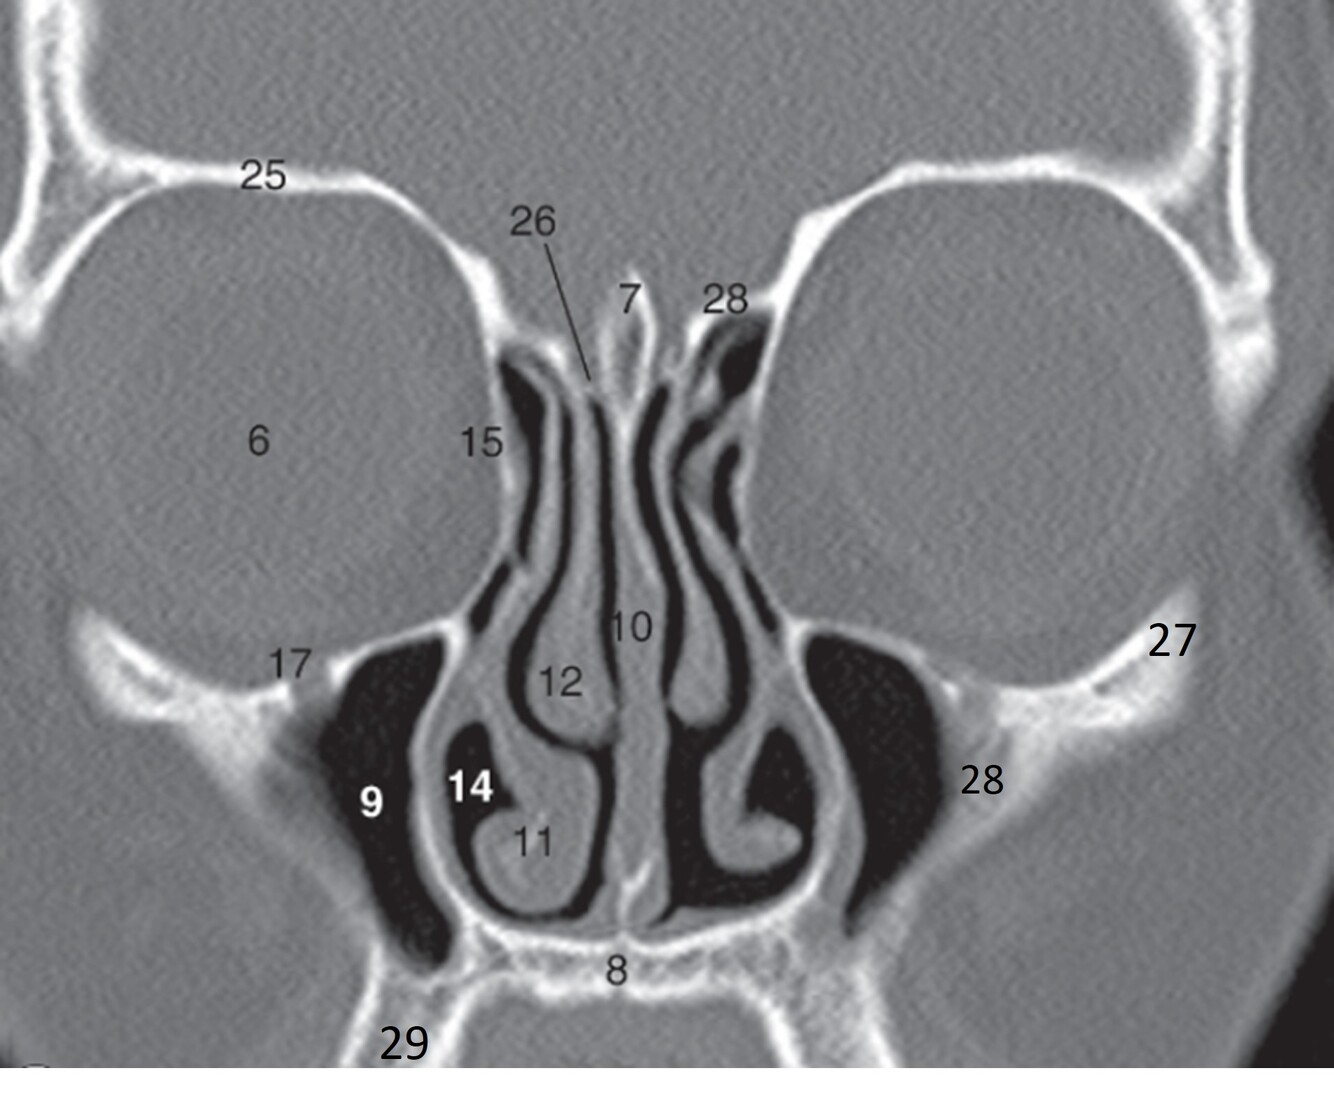

6

Label 7-12

7=Crista Galli (Ethmoid)

8.=Hard palate (Maxilla)

9=Rt. Maxillary sinus

10=Nasal septum

11=Rt. Inferior nasal concha

12=Rt. Middle nasal concha

7

Label 14,15,17,25,26

14=Rt. Inferior nasal meatus

15=Rt. Lamina papyracea (Ethmoid)

17=Rt infraorbital foramen (Maxilla)

25=Rt Orbital roof (frontal bone)

26=Rt Cribriform plate (Ethmoid)

8

Label 27-29

27=Lt Zygoma

28=Zygomatic process (Lt Maxilla)

29=Alveolar process (Rt Maxilla)

9

Label 8,9,10,12,13,18

8=Hard palate (Maxilla)

9=Lt maxillary sinus

12= Rt. Middle nasal concha

13=Rt. Superior nasal concha

18=Rt. Ethmoid air cells